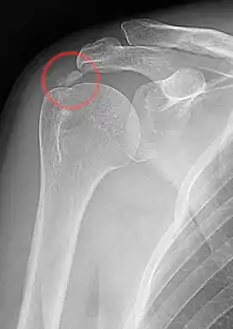

غالبا ما يتفاقم الألم عن طريق رفع الذراع فوق مستوى الكتف أو عن طريق الاضطجاع على الكتف . الألم قد يوقظ المريض من النوم، قد توجد شكاوى اخرى مثل : صلابة المفصل، تعلقه عن الحركة، العض، وضعف الكتف . رواسب الكالسيوم تكون مرئية في الأشعة السينية كأنها كتل متميزة أو مناطق غائمة. الرواسب تبدو غائمة في الأشعة السينية إذا كانت في عملية إعادة امتصاص وفي هذه الحالة تسبب معظم الألم، الرواسب البلورية عندما تكون في طور السكون مثل معجون الأسنان فهي مرحلة إعادة الامتصاص. ومع ذلك، العلاقة بين رواسب الكالسيوم ضعيفة وتظهر بوضوح في الأشعة السينية وهي متماسكة عند الوخز بالإبرة، الأشعة فوق الصوتية أيضا مفيدة لتصوير الرواسب الكلسية وبشكل وثيق يرتبط بمرحلة المرض .